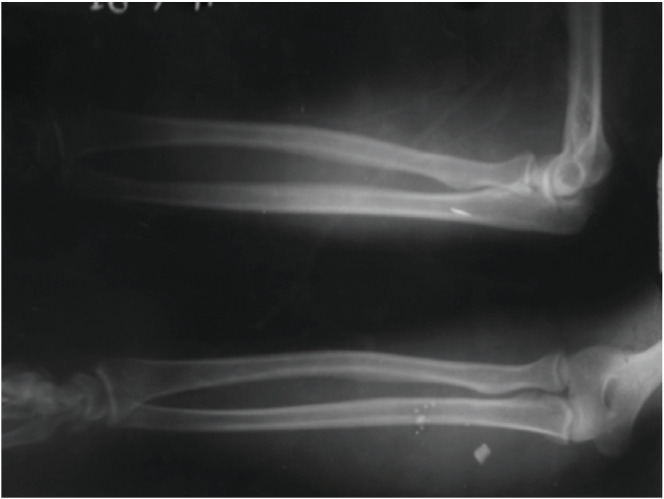

Materials and methods: This presentation is on a series of 18 cases of nerve injuries among industrial workers located from finger level up to the arm excluding the brachial plexus due to metallic foreign bodies entering while operating lathe machines over a period of two years with patients being followed-up over a one year period.

Results: Mean age in this series was 31.3 years with age range 16-40 years and all were males. Two patients had more than one nerve involvement and one patient had associated vascular injury. All the patients showed functional improvement. Most common nerve injured was median nerve. Most common site for nerve injury was forearm. Combined lesions most commonly involved the ulnar and median nerves.